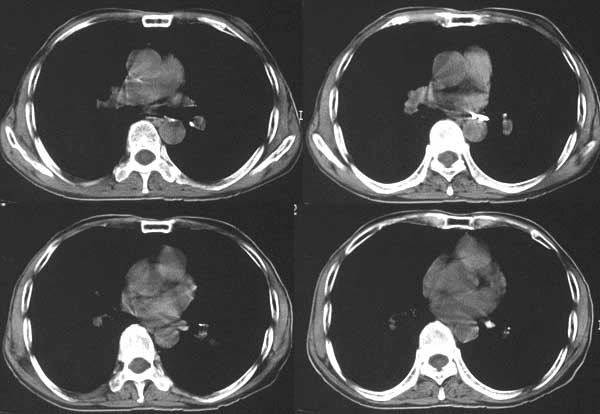

本例病人肺内多发结节灶、双侧肋骨破坏、胸椎椎体及椎弓破坏应是肾癌转移。请大家分析气管内结节灶性质?另外还得麻烦领导给删掉那多余的那幅图。谢谢了!

支持肺内 肋骨 椎体转移。

支持肺内,椎体,肋骨,腹膜后淋巴转移.

支持肺内,椎骨,肋骨,腹膜后淋巴结转移

1、支持肺内 肋骨 椎体转移。

左侧肾癌伴腹膜后淋巴结、胸椎、双肺内转移。

肾癌.双肺,胸椎及肋骨转移.